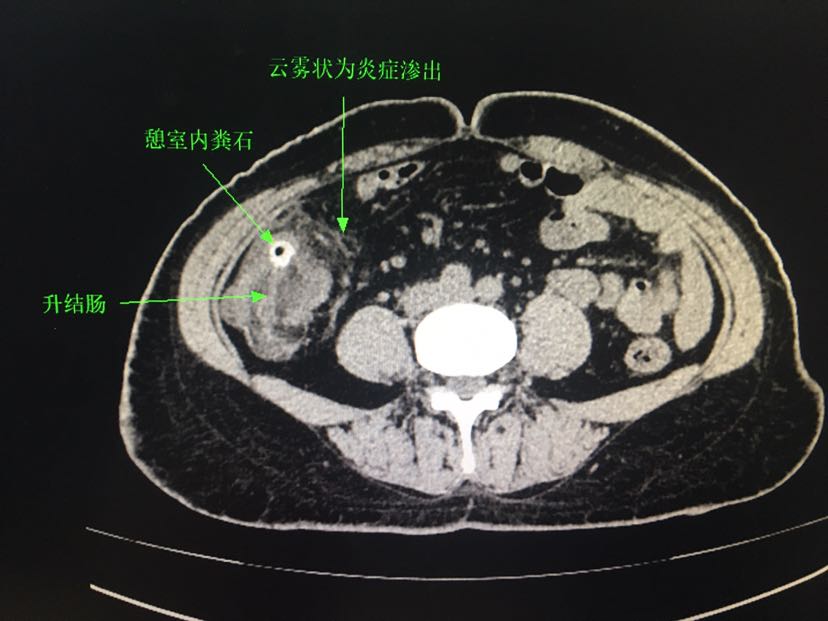

盆腔可能阑尾管腔扩张,周围有渗液.不排除回肠憩室粪石嵌顿引起.